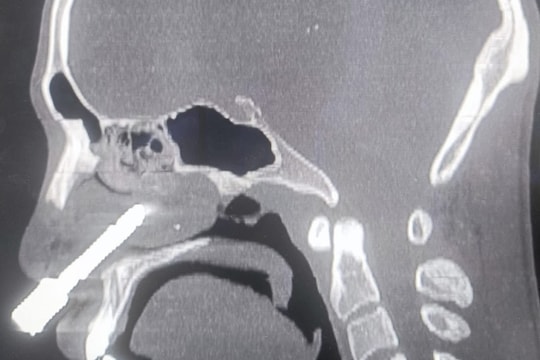

Hy hữu: Nam nhanh niên bị mũi khoan đá đâm xuyên hốc mũi

Ngày 5/8, Bệnh viện Đa khoa tỉnh Thanh Hóa cho biết, mới thực hiện thành công ca phẫu thuật cấp cứu hy hữu, lấy mũi khoan đá dài gần 8cm cắm sâu trong hốc mũi một nam bệnh nhân.